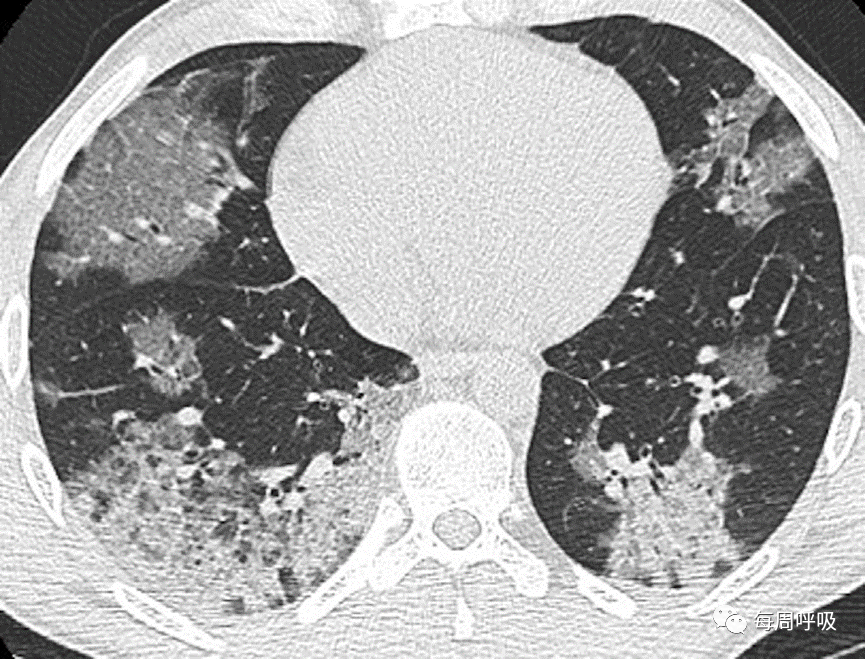

图27 COVID-19和机化性肺炎(OP)。一名55岁男性确诊COVID-19, CT表现典型。肺中部(A)和肺下段(B)的CT平扫图像显示右肺上叶磨玻璃影(GGO)伴小叶内间隔增厚,各肺下叶周边均有GGO和实变影,左肺下叶为小叶周围型。这些表现也是典型的OP。